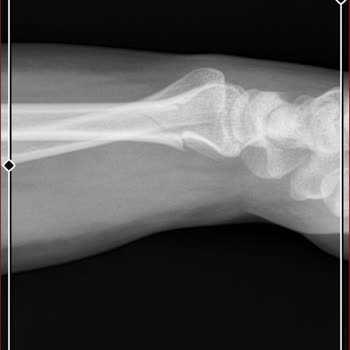

Şikayetim Taksim Eğitim ve Araştırma Hastanesi'nden! 19 Kasım gece oğlum bileğini kırmış, gittik hastanenin aciline röntgen ve MR çekildi, hiçbir şey yok dediler, sadece incinmiş dediler, korse tak geçer bir iki güne ama çocuk gece uyumadı ağrıdan, el balon gibi şişti. Götürdüm O***'ne tekrar film ç...